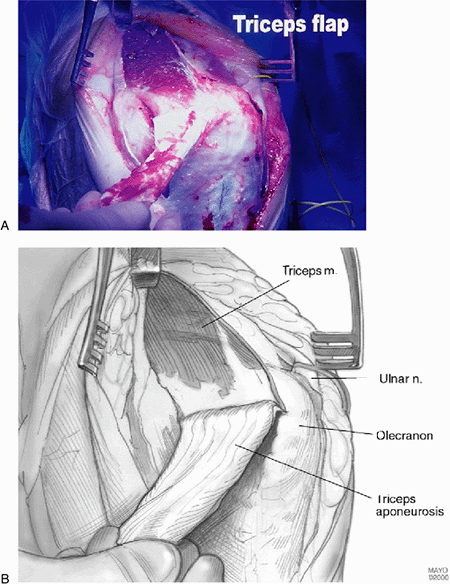

![]() |

|

Figure 17-6. A,B:

The authors prefer the Van Gorder “turndown procedure” of a sleeve of fascia. The triceps is then split to expose the distal humerus and ulna. |

Figure 17-17. A,B:

A triceps splitting incision reflecting the triceps medially and laterally and from the subcutaneous border of the ulna is the most commonly used exposure. |